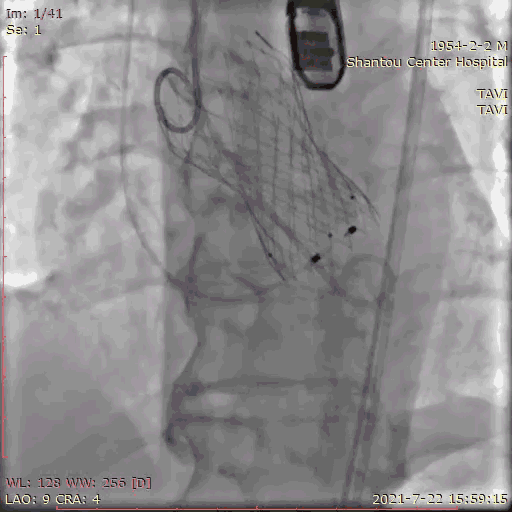

主动脉根部造影

临时起搏器植入后,辅入路穿刺,猪尾导管置于无冠窦底进行主动脉根部造影。

初步判断释放体位是否合适。

观察瓣叶活动度、是否合并反流,有利于跨瓣。

左右冠通畅,存在一定反流,有一定耐受能力,球扩时,循环崩溃风险较小。

左冠窦瓣叶活动度高、无钙化,无冠窦右冠窦活动度减轻,且钙化集中在基底部,右冠风险较左冠低。